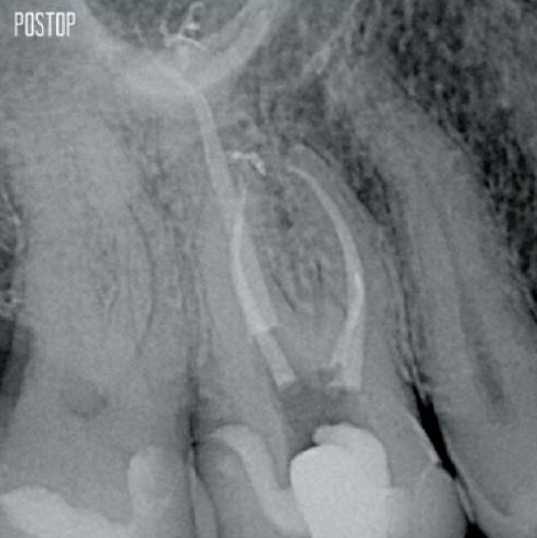

Fotos cortesía del Dr. Ahmed Salman

TruNatomy® conserva la mayor cantidad de dentina posible1 y ofrece una solución completa que incluye irrigación y obturación coincidentes.

Más conservación de dentina. Se garantiza la conformación, irrigación y obturación adecuadas.